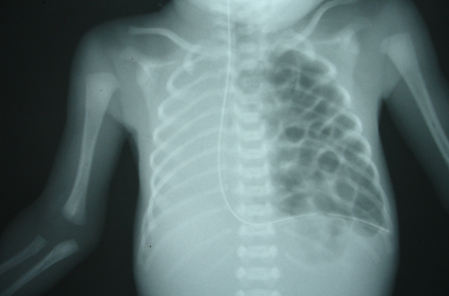

13. Congenital Diaphragmatic Hernia

► Left hemithorax filled with cyst like loops of bowel

► Mediastinal shift to right side